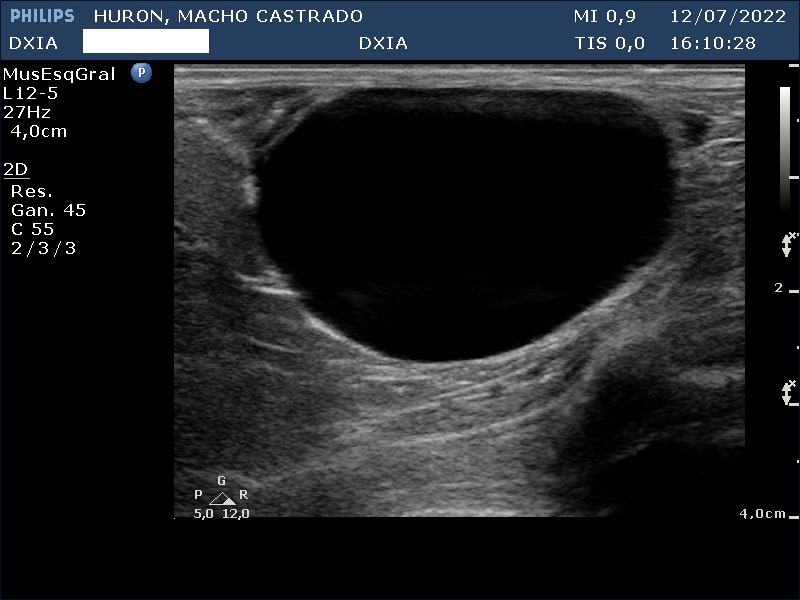

Estudio de ecografía abdominal

En esta ocasión os queremos presentar el caso de hurón (macho castrado) al que, debido a los síntomas que presentaba, tuvimos que realizarle un estudio ecográfico abdominal.

Presenta convulsiones así como hipoglucemias con picos de hiperglucemia por lo que su veterinario decide realizar un estudio de ecografía abdominal.

Hallazgos ecográficos